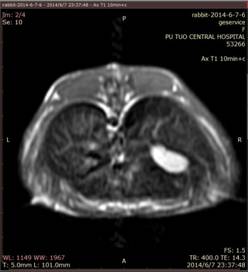

Resovist是一种器官特异性MRI造影剂,用于检测和表征特别小的肝脏局灶性病变,是由包裹有羧基葡聚糖的超顺磁性氧化铁( SPIO )纳米颗粒组成,它们通过吞噬作用在肝脏网状内皮系统( RES )的细胞中积累。Resovist注射液在网状内皮细胞中的摄取导致正常肝实质在T2和T1加权图像上的信号强度降低。大多数恶性肝肿瘤不含RES细胞,因此不摄取铁颗粒。所得到的成像效果是肿瘤(亮)和周围组织(暗)之间的改善的对比度。resovist可以静脉推注的形式注射,这允许立即对肝脏成像并减少总检查时间。团注后的动态成像策略支持病变特征。在全面的临床试验中,它显示出极好的安全性。2001年,Resovist获准进入欧洲市场。